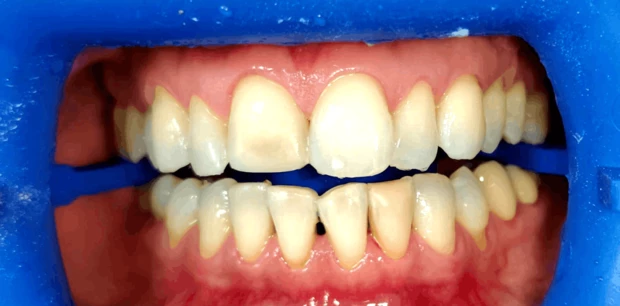

Реставрация, отбеливание

Восстановление эстетики улыбки винирами E.max

Пациентка Н., 30 лет обратилась с жалобами на эстетическую неудовлетворенность внешним видом зубов из-за щелей. Проведено лечение винирами Emax.